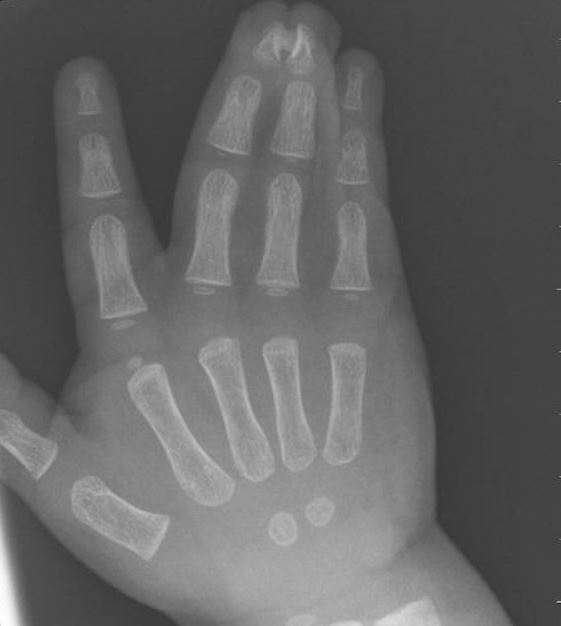

Yhdyssormisuus voidaan todeta ilman kuvantamistutkimuksia. Röntgenkuvaus tehdään tapauskohtaisesti, kun halutaan selvittää tarkemmin mahdollista luista poikkeavuutta.